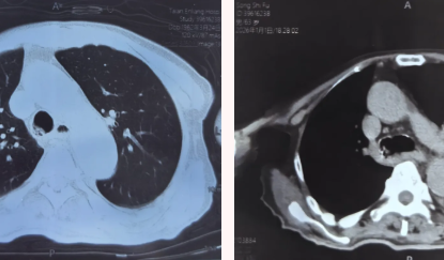

鞍山市首例!我院成功实施经电子支气管镜激光切除术

近日,鞍钢集团公司总医院呼吸与危重症医学科联合麻醉科,成功完成鞍山市首例经电子支气管镜激光切除主气道恶性肿瘤手术。这一高难度手术的成功,不仅挽救了患者生命,也标志着我院在急危重症气...